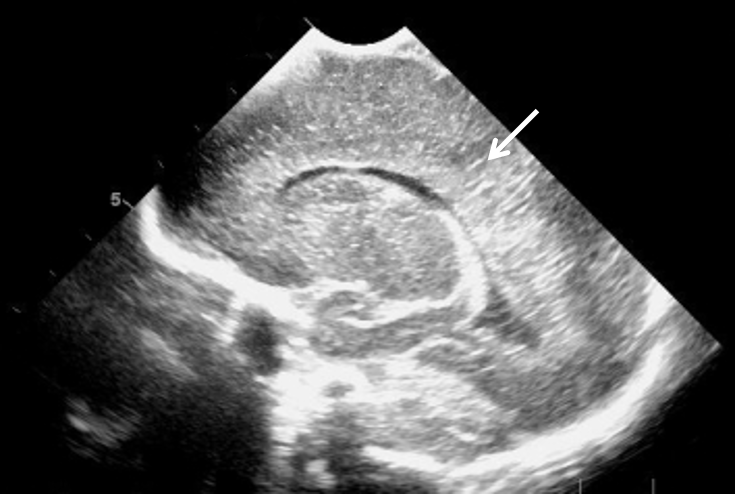

Neonatology Grade 1 PVL 5 Image